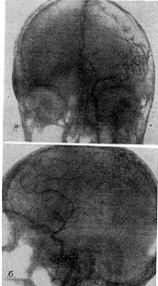

К местным изменениям могут быть отнесены деструкции костей черепа и позвоночника и их отверстий, связанные с давлением прилежащих к ним опухолевых узлов. Развитие нейрофиброматозных узлов, связанных с черепномозговыми нервами, преимущественно VIII и иногда V пары, сопровождается деструкцией костной ткани на месте расположения опухолей. Так, при наличии неврином слуховых нервов внутренние слуховые проходы обычно резко расширены: при двусторонних невриномах - с двух сторон (рис. 1), при односторонних - с одной. Верхушки пирамид, при этом истончены и деструктированы (рис. 2). Расширение внутреннего слухового прохода и деструкция (узура, порозность) верхушки пирамиды височной кости, которые всегда можно увидеть на прицельных рентгенограммах этой области, являются одним из основных краниографических. симптомов невриномы VIII нерва.

Рис. 2. Больная Г., 15 лет. Расширение внутренних слуховых проходов с разрушением верхней грани пирамид (снимки пирамид височных костей по Stenvers).